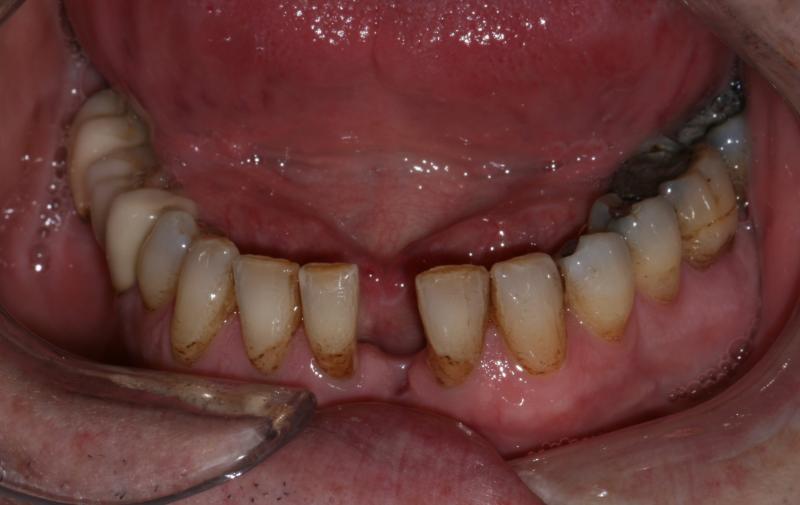

Traditional bridge - Before

Adhesive bridge - Before